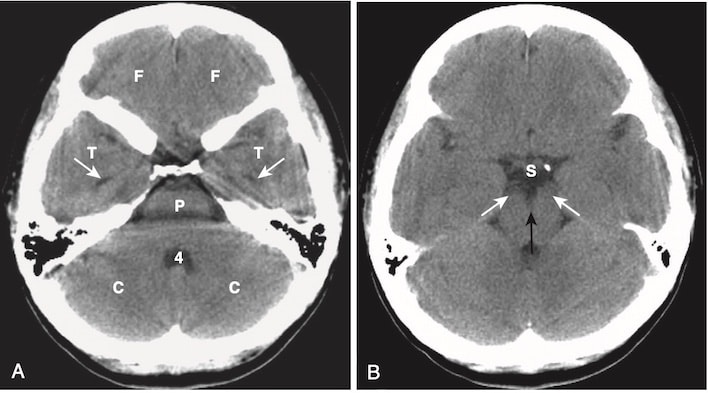

- Ở hố sau (posterior fossa), não thất 4 xuất hiện như một cấu trúc hình chữ U ngược. Tương tự như tất cả các cấu trúc chứa dịch não tủy (CSF, cerebrospinal fluid), nó thường có màu đen trên CT. Phía sau não thất thứ 4 là các bán cầu tiểu não, và phía trước là cầu não và hành tủy. Lều tiểu não (tentorium cerebelli) ngăn cách các thành phần dưới lều của hố sau (hành tủy, cầu não, tiểu não và não thất 4) với khoang trên lều. (Hình 1A)

- Bể chứa gian cuống (interpeduncular cistern) nằm trong não giữa và ngăn cách các cặp cuống não, các cuống này nổi lên từ bề mặt trên của cầu não. Bể chứa trên tuyến yên (suprasellar cistern) nằm trước bể chứa gian cuống và thường có hình dạng giống như hình sao năm hoặc sáu cánh. (Hình 1B)

- Các khe sylvian đối xứng hai bên và chứa dịch não tủy. Chúng tách thuỳ thái dương khỏi thùy trán và thùy đỉnh. (Hình 1C)

- Nhân bèo (lentiform nucleus) bao gồm bèo sẫm (putamen) (nằm ngoài) và cầu nhạt (globus pallidus) (nằm trong) (Hình 1E). Não thất ba có dạng rãnh và nằm ở đường giữa. Ở phía sau của não thất ba là tuyến tùng. Phía sau hơn nữa là bể chứa củ não sinh tư (quadrigeminal plate cistern). (Hình 1C)

- Sừng (trán) trước của não thất bên ôm lấy đầu của nhân đuôi (Hình 1D, E). Hai sừng trước được ngăn cách bởi vách trong suốt (septum pellucidum) ở đường giữa. Sừng thái dương, bình thường rất nhỏ, ở thấp hơn và nằm trong thùy thái dương. Sừng sau của não thất bên (sừng chẩm) nằm trong thùy chẩm. (Hình 1F) Phần cao nhất của hệ thống não thất là các thân của não thất bên.

Hình 1. Chụp cắt lớp vi tính đầu bình thường không cản quang.